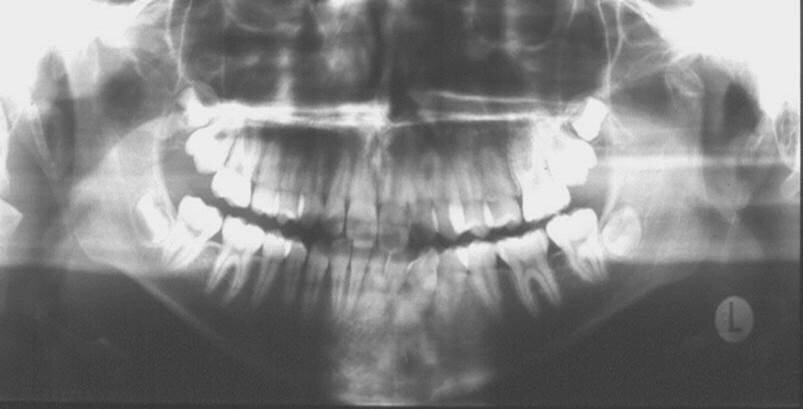

Condylar fracture

Condylar fractures in growing individuals are usually the results of accidents and sports (Figure 4). In children they are often overlooked by parents and physicians since short time after the injury symptoms of pain usually disappear. The majority of condylar fractures in children, if properly diagnosed and managed by short-term intermaxillary fixation and subsequent physiotherapy, do not lead to morphological and functional problems. However, no diagnosis of condyle fractures may lead to face asymmetries, severe malocclusion and TMJ ankylosis (5).

Figure 4. Panoramic radiograph of a 15-year-old girl showing fracture of the left condyle.